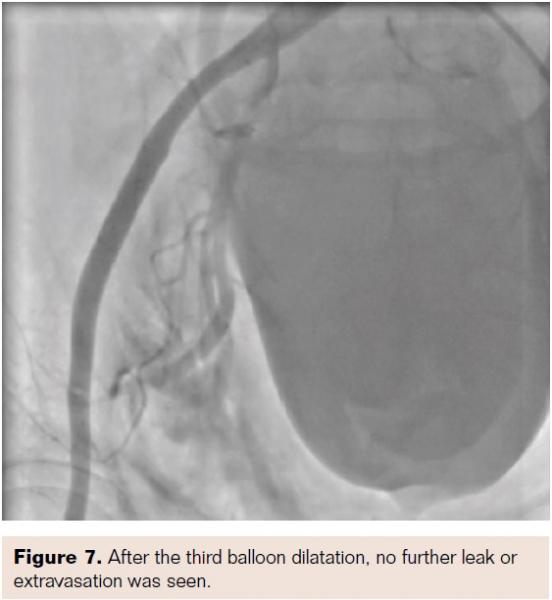

There was a small leakage seen after this from the right SFA (Figure 6). On waiting further, no further dye leakage was seen on the last check shot (Figure 7). The patient remained stable hemodynamically, and a follow-up ultrasound was performed. This showed a small hematoma in the right femoral area of 5 x 5 cm. However, the patient improved and was discharged after a course of antibiotics (total hospital stay after the procedure was 9 days).